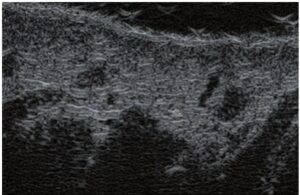

Les traitements laser consistant en une fermeture transcutanée des vaisseaux sont de plus en plus populaires. L’essence de ces traitements réside dans l’envoi d’un faisceau lumineux sur le vaisseau, qui est absorbé par l’hémoglobine contenue dans les érythrocytes et transformé en énergie thermique. Cela conduit à chauffer la paroi du vaisseau et à sa coagulation. Alors que dans le cas des légères télangiectasies, l’effet est obtenu immédiatement, dans les veines réticulaires, la fermeture se produit plusieurs semaines après la procédure(9). L’efficacité de la thérapie dépend de la sélection adéquate des paramètres de traitement. La détermination de l’emplacement des vaisseaux dans les couches de la peau et de leurs diamètres est d’une grande importance. Ces deux paramètres peuvent être spécifiés avec précision en EHF. Sur la base des résultats échographiques, le type de laser est sélectionné, ce qui implique la sélection de la longueur d’onde, de la durée d’impulsion, du diamètre du spot et de l’énergie d’impulsion(7). Dans le traitement au laser, l’EHF est également utile comme méthode de surveillance de l’exactitude du traitement et de son efficacité. Pendant la procédure, l’échographie peut aider à garantir que l’énergie laser atteint le vaisseau – son diamètre devrait diminuer immédiatement (fig. 5). Si un tel effet n’est pas détecté, les paramètres de traitement doivent être vérifiés. De plus, il convient de vérifier si la tête laser est correctement appliquée sur la peau. L’EHF est également utilisée pour évaluer l’efficacité des procédures effectuées. Les paramètres utiles dans une telle évaluation sont : présence ou absence de perfusion dans le vaisseau, présence ou absence d’un thrombus dans la lumière du vaisseau, diamètre du vaisseau et épaisseur de sa paroi.